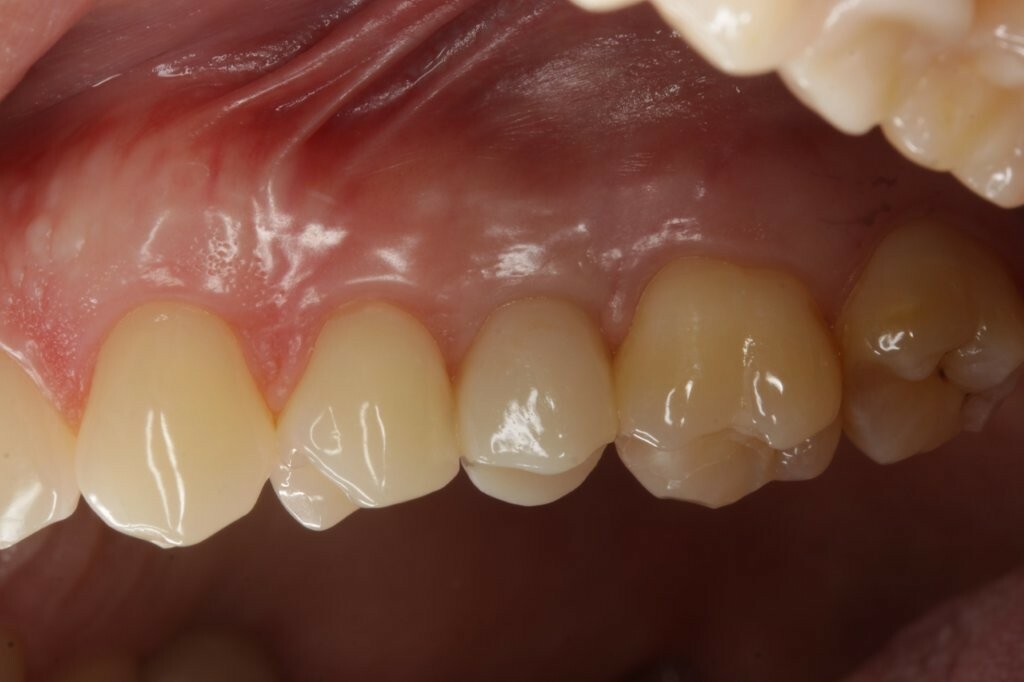

Ein Patient mit einem gepflegten Gebiss in eugnather Verzahnung (Abb. 1) stellte sich aufgrund einer Kronen-Wurzelfraktur an Zahn 25 in der Praxis vor. Die Untersuchung ergab, dass der Zahn aufgrund einer Fraktur des palatinalen Höckers mit subkrestalem Frakturverlauf (Abb. 2) nicht erhaltungswürdig war.

Zu Beginn wurde das Einzelzahnimplantat (Conelog ScrewLine Titanimplantat, 3,8 x 9,0 mm, Camlog) in Regio 25 gesetzt, geschlossen eingeheilt und nach Freilegung mit einem Gingivaformer (Conelog Gingivaformer, wide body, 3,8 x 6,0 mm, Camlog) versehen (Abb. 3). Mithilfe eines VITA-Farbschlüssels (VITA Zahnfabrik) wurde für die spätere Krone die Farbe A3 bestimmt (Abb. 4).